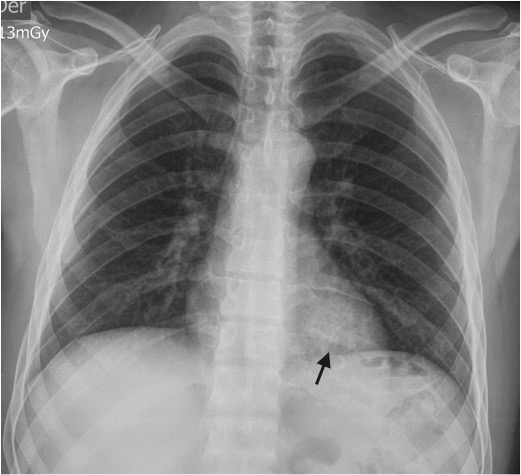

Paciente de 39 años con antecedente de Síndrome de Tolosa Hunt, quien ingresa al servicio de urgencias por disminución de la agudeza visual y cefalea. Dado el antecedente se considera realizar estudios complementarios para descartar enfermedad granulomatosa, como causa del síndrome, encontrando hallazgos incidentales en las imágenes del tórax. El secuestro pulmonar es una anomalía congénita caracterizada por tejido pulmonar displasico, sin conexión normal con la vía aérea, irrigado por la circulación arterial sistémica. Hay dos tipos de secuestros, el intralobar y el extralobar. El intralobar (75%), puede ser congénito o adquirido como secuela de infecciones recurrentes localizadas, está cubierto por pleura del pulmón normal adyacente y generalmente su drenaje venoso es a través del sistema venoso pulmonar ipsilateral. El secuestro extralobar (25%), es considerado una anomalía congénita, está revestido por su propia pleura y su drenaje venoso es sistémico. Tanto el secuestro intralobar como extralobar reciben suplencia arterial sistémica. En los estudios de imágenes, el secuestro se puede presentar como consolidación focal, nódulo o masa, de localización paravertebral, contiguo al hemidiafragma, en los lóbulos inferiores (segmento posterior), con mayor frecuencia en el lado izquierdo (98%) y con una suplencia arterial anómala dada por una o múltiples ramas (15%) generalmente de la aorta torácica y su drenaje puede ser al sistema venoso pulmonar y con menor frecuencia a la circulación sistémica.